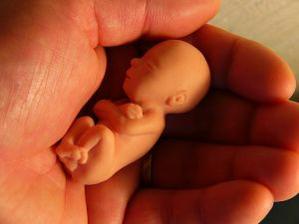

Jak asi víte, těhotenství je členěné na tři časové úseky, kterým říkáme trimestry – každý z nich trvá tři měsíce. Každý z trimestrů je zcela specifický, probíhají v něm určité charakteristické změny, podstupuje se vyšetření a nesou s sebou jiné pocity a obavy nastávající maminky.

Lékaři počítají týdny těhotenství od prvního dne poslední menstruace před otěhotněním. V prvních dvou týdnech tehotenství tedy žena těhotná není, protože k oplodnění vajíčka dochází až zhruba 14 až 21 dní od začátku menstruace.

1.-2. týden těhotenství

Vajíčko ve vejcovodu čeká zhruba 12 až 24 hodin na příchod spermií. V ejakulátu je v průměru 250 milionů spermií, z toho pouze zhruba 400 se dostane až k vajíčku ve vejcovodu, přičemž cesta z pochvy do vejcovodu trvá spermiím až 10 hodin. Obvykle pouze jedna spermie uspěje a pronikne po zhruba 20 minutách snahy do vajíčka. Tím dojde ke vzniku oplodněného vajíčka, tzv. zygoty. V příštích 10 až 30 hodinách dochází ke splynutí genetických informací vajíčka a spermie. Pohlaví dítěte je určeno již v této chvíli – pokud spermie nese chromozom Y, narodí se chlapec, pokud chromozom X, narodí se dívka.